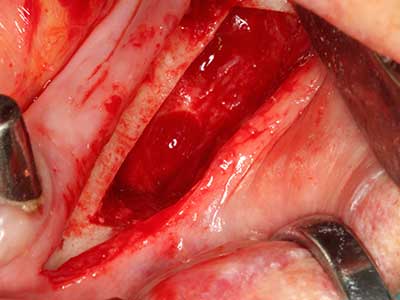

Пиезохирургията има допълнителни предимства при събиране на костни блокове. В допълнение към високата прецизност при остеотомията, описана по-горе, употребата на фините режещи накрайници значително намаляват загубата на материал. Голяма загуба на материал по време на събиране може да се очаква с дебелите накрайници, особено при употреба на борери Линдеман (Lakshmiganthan, Gokulanathan et al. 2012). Базалното разделяне, което е необходимо, особено за присадка на блок при ретромолар, е улеснено от специално създадени правоъгълни триони. В резултат на това, пиезохирургията е разглеждана като прецизна, улеснена и безопасна процедура за събиране на костни блокове в ретромоларното пространство (Happe 2007) (Фиг. 1-12).

Когато се извършват хирургични процедури върху кост в непосредствена близост до чувствителни структури като кръвоносни съдове или нерви, ротиращите инструменти създават значителен риск за ятрогенно нараняване. Пиезоелектрическите апарати могат да бъдат от помощ при препарация на костно покритие и отстраняване на твърда кост близо до нерви, особено за оголване на нервите след ятрогенно нараняване, както и по време на латерализация на нервите за резекционни и реконструктивни процедури или поставяне на имплант (Фиг. 17-20). Лекият контакт между пиезонакрайника и нерва по принцип не води до нараняване, но ако действате непредпазливо с трионообразни движения или приставки за остатъчен костен субстрат, може да причините временно или перманентно увреждане на нерва. Въпреки това, рискът от увреждане се счита за много по-малък, отколкото при употреба на триони или ротиращи инструменти (Pereira, Gealh et al. 2014).